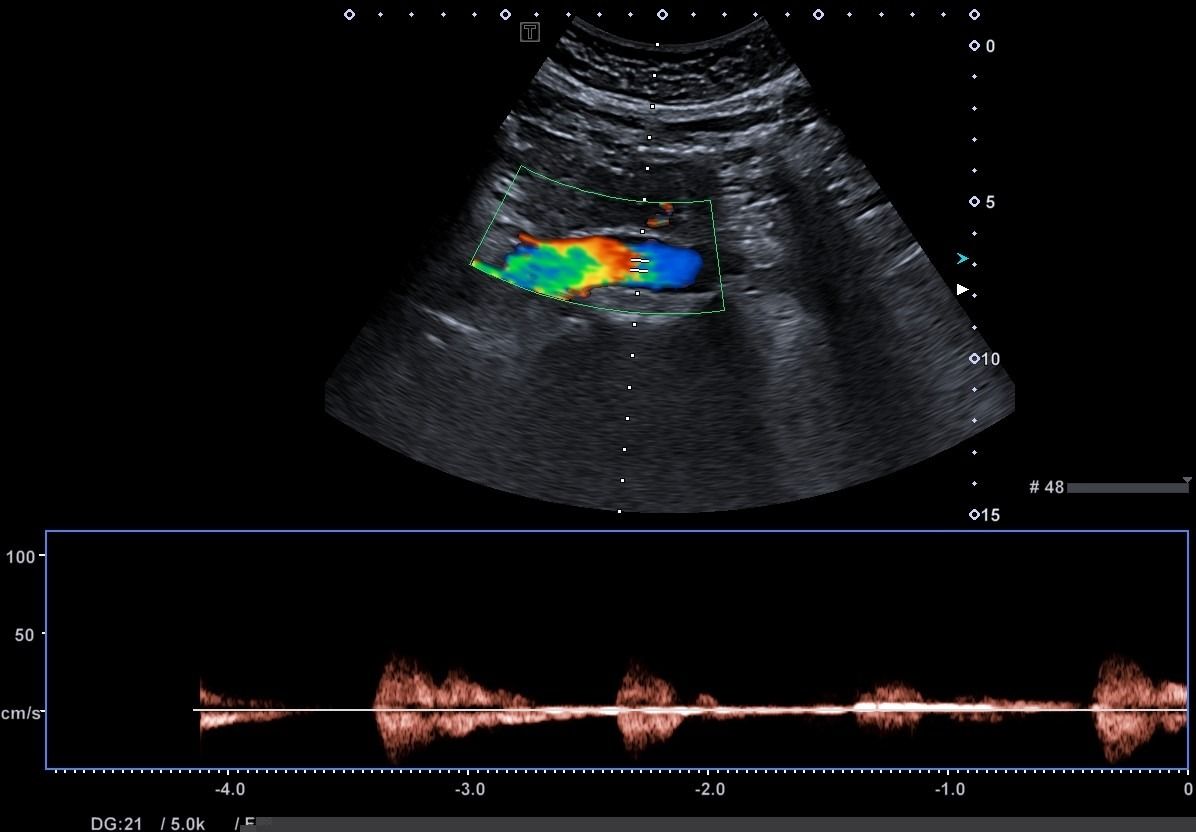

- Αιμοδυναμικές Διαταραχές: Mε τη χρήση του Έγχρωμου και του Παλμικού Doppler μπορούν να μελετηθούν οι ταχύτητες της αιματικής ροής και να ανιχνευθούν πιθανές αιμοδυναμικές διαταραχές.

- Αγγειακή Στένωση: Η αξιολόγηση της αιματικής ροής μπορεί να οδηγήσει στη διάγνωση στένωσης των αγγείων και να υπολογιστεί ο βαθμός της στένωσης.